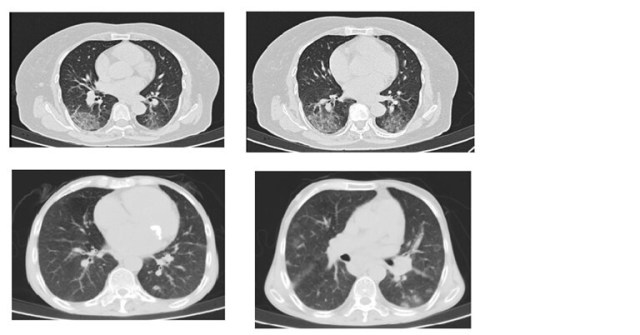

COVID commonly involves bilateral multifocal areas of the lungs. Single lobe involvement was also observed in a small number of patients. The right lower lobe, being a short and thick anatomic structure, can easily be invaded by the virus. Sub-pleural distribution of the disease is commonly seen because of possible location of target cells in the lower airway. Lesions around the bronchovascular pathways can be explained by the spread of infection along the intralobular interstitial tissues. Inflammation starts by early invasion of cortical pulmonary airways and alveolar epithelium, and gradual extension towards the central area.

Chest CT can be used to determine disease severity, progression, and staging of COVID-19 pneumonia. Pathological succession and CT features can be very well correlated.

Early stage (days 0-4)

Ground-glass opacities

Progressive stage (days 5-8)

Crazy paving patterns suggestive of recruitment of inflammatory cells to the lung interstitial space

Peak stage (days 10-13)

Consolidation due to tissue organisation and diffuse alveolar damage

The most common CT findings in COVID-19 are ground glass opacities and consolidation noticed in 95% and 72% of the patients respectively. Ground glass opacities have been considered to be the result of serous inflammatory exudative reaction from lung alveoli. Copious amounts of such inflammatory exudation ultimately forms consolidation. Studies have reported prominent bilateral consolidation on CT scans in ICU patients. Ground-glass opacities and little areas of consolidations are seen in patients with mild symptoms of the infection not mounting to the admission.

Clinical implications of these findings are that manifestation of the disease in early stage are ground-glass opacities and as the severity progresses consolidation becomes eminent in wider areas. In other words, such changes are predictive of rising possibilities of critical complications like acute respiratory distress syndrome or acute lung injury.

In a retrospective study, authors found patients with initial negative RT-PCR having mostly ground glass opacities and small areas of consolidation as compared to patients with positive initial RT-PCR results. Patients with mild lung injury as suggested by smaller consolidation areas on CT scan are having higher chances of getting negative initial RT-PCR result.